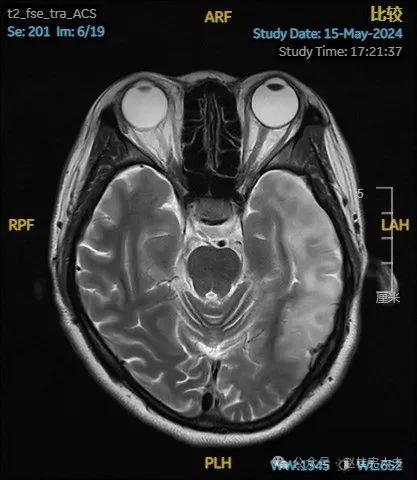

入院后给予精氨酸,左卡尼丁,辅酶Q10,维生素E等治疗。患者病情稳定好转中,2天后意识清楚,语言表达仍欠佳。当天复查颅脑磁共振如下:

以上为患者发病后3次的颅脑磁共振片子,临床诊断基本上可以确认了,希望患者逐渐恢复!